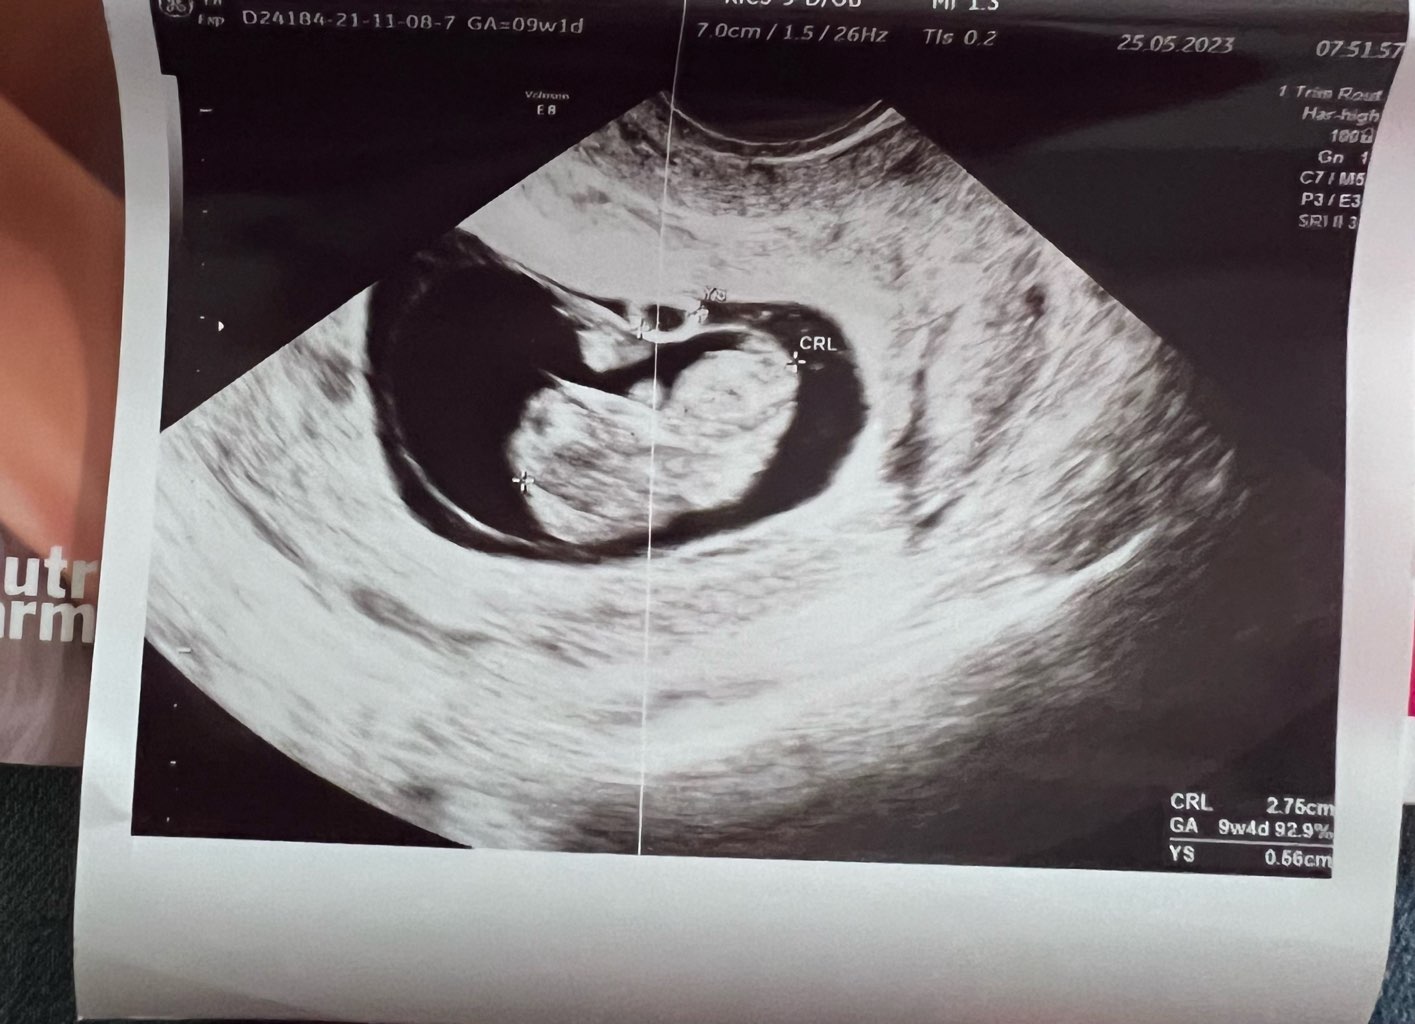

Dzień doberek! Jak tam się czujecie? Ja po wizycie i wyglądamy teraz tak. Prenatalne umówione na 14.06

• IMG_6028.jpeg

IMG_6028.jpeg

132,2 KB · Wyświetleń: 129